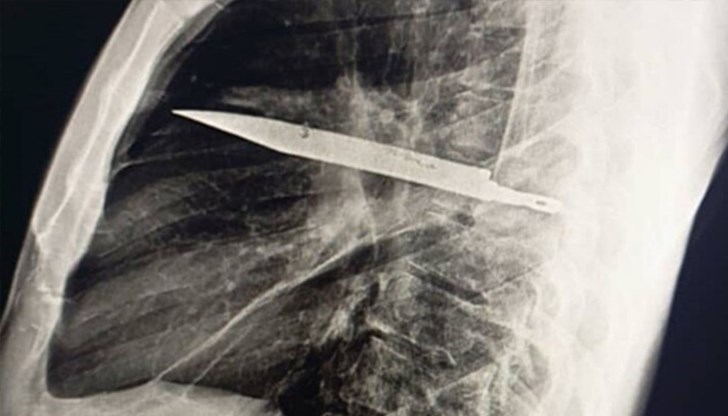

Истинската изненада дошла при образните изследвания. Рентгеновата снимка разкрила голям метален нож, заседнал в гръдната кухина – точно в областта, където се намират сърцето и белите дробове. Острието преминавало от задната страна на гръдния кош към предната, като било проникнало през гърба близо до дясната лопатка, вмъкнало се между петото и шестото ребро и достигнало с върха си до пространството между третото и четвъртото ребро отпред.

Компютърната томография показала и зараснали счупвания на лопатката и няколко ребра. Около острието имало натрупани слоеве гной и мъртва тъкан, което вероятно е причината за появилото се възпаление след толкова години.